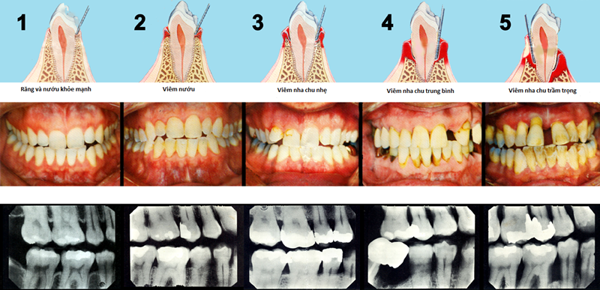

1. Các giai đoạn của bệnh viêm nha chu

Các giai đoạn của viêm nha chu

Bệnh viêm nha chu tiến triển qua 4 giai đoạn:

• Giai đoạn 1: Vôi và cao răng hình thành do vệ sinh răng miệng không sạch sẽ, từ đó vi khuẩn tích tụ thành mảng bám ở kẽ răng, cổ răng, viền lợi và gây kích thích nướu, dẫn đến viêm lợi.

• Giai đoạn 2: Sưng phồng và chảy máu ở lợi, đặc biệt là khi nhai thức ăn hoặc chải răng.

• Giai đoạn 3: mủ ở nướu do vi khuẩn tích tụ lâu ngày mà không được điều trị kịp thời.

• Giai đoạn 4: Tụt lợi do tình trạng xương ổ răng bị phá hủy cấu trúc. Khi các tổ chức xung quanh răng không còn chắc chắn sẽ khiến răng bị lung lay và có thể dẫn đến mất răng.